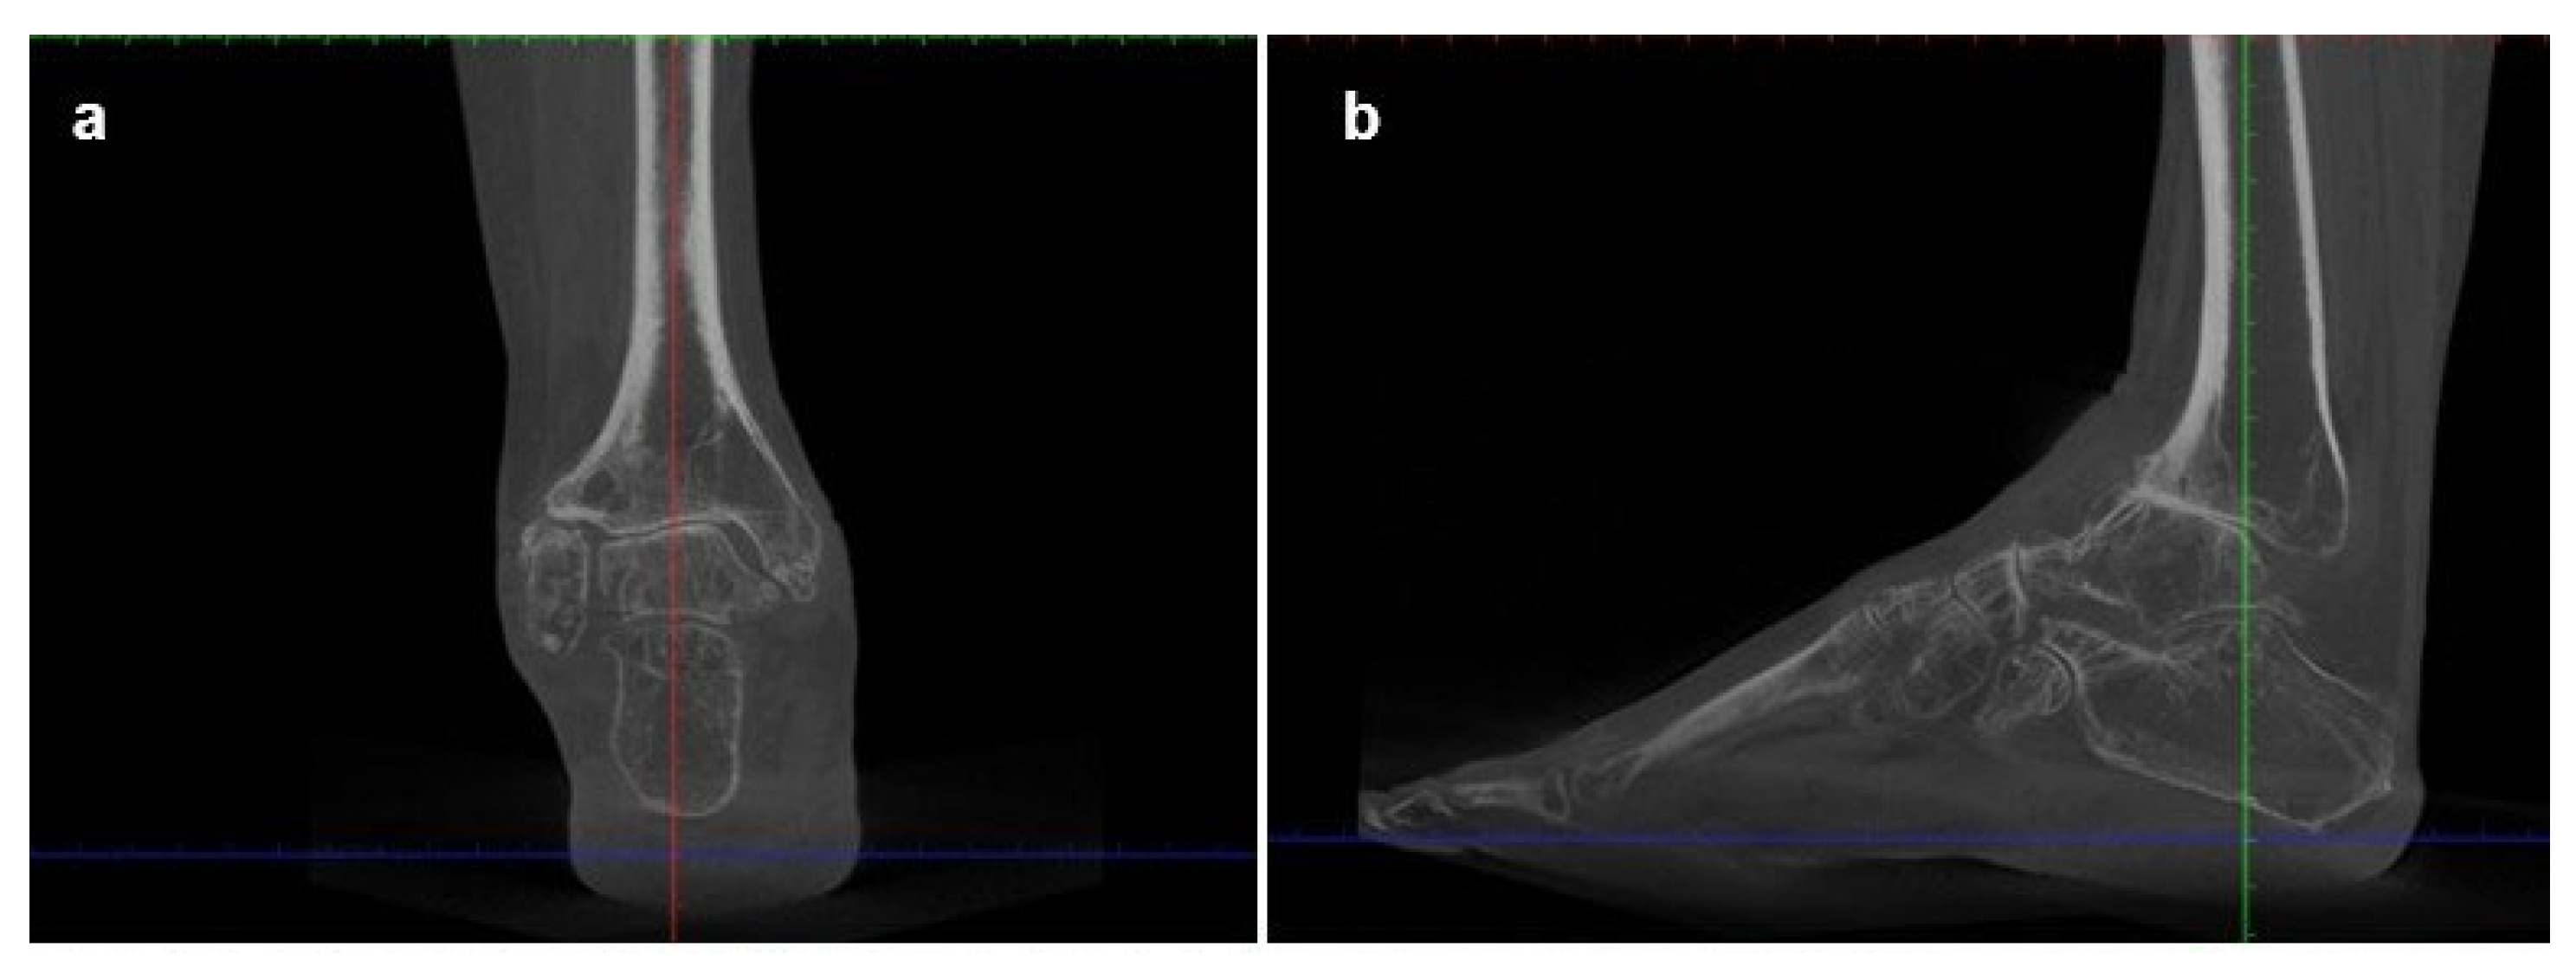

Imaging, including bilateral weight-bearing X-rays (Figure 4) and WBCT (Figure 5), demonstrated end-stage tibiotalar osteoarthritis (Kellgren–Lawrence grade 4[8]) with distal tibial and distal fibular bone deformity. The ankle showed a valgus alignment with posterior shift of the talus. Early degenerative changes were also observed in the talonavicular and subtalar joints. The midshaft of the fibula displayed residual deformity from previous surgical procedures. Radiographic measurements are summarized in Table 2. The patient gave informed consent for the publication of his clinical details and images.

Figure 5. Preoperative weight-bearing computed tomography (WBCT) scans of Case two: (a) coronal and (b) sagittal views showing severe tibiotalar osteoarthritis with valgus malalignment, distal tibial and fibular deformities, posterior talar displacement.